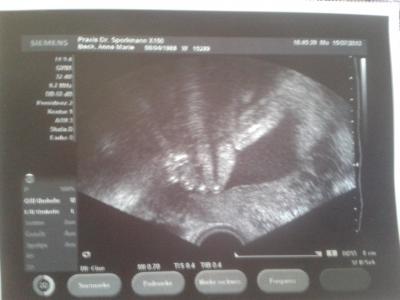

war heute bei der vertretungsärztin weil meine im urlaub ist und ich war echt total begeistert zuerst abgetastet 2 finger über nabel und herztöne auch okay. dann zuckertest... echr eklig das zeug. wenn was ist melden sie sich. dann hat sie noch einen us von unten gemacht. mm alles zu gbh 5 cm alles super. dann fing sie aufeinmal zu lachen und sagte " wie niedlich der kleine kratzt sich gerade mit der hand am po" was soll ich dazu sagen. typisch papa halt anbei ein foto vom händchen

Bild zu zurück vom fa :-) - Forum für November - Mamis

achja und der kleine liegt in bel. hat aber noch genung platzt meinte die ärztin